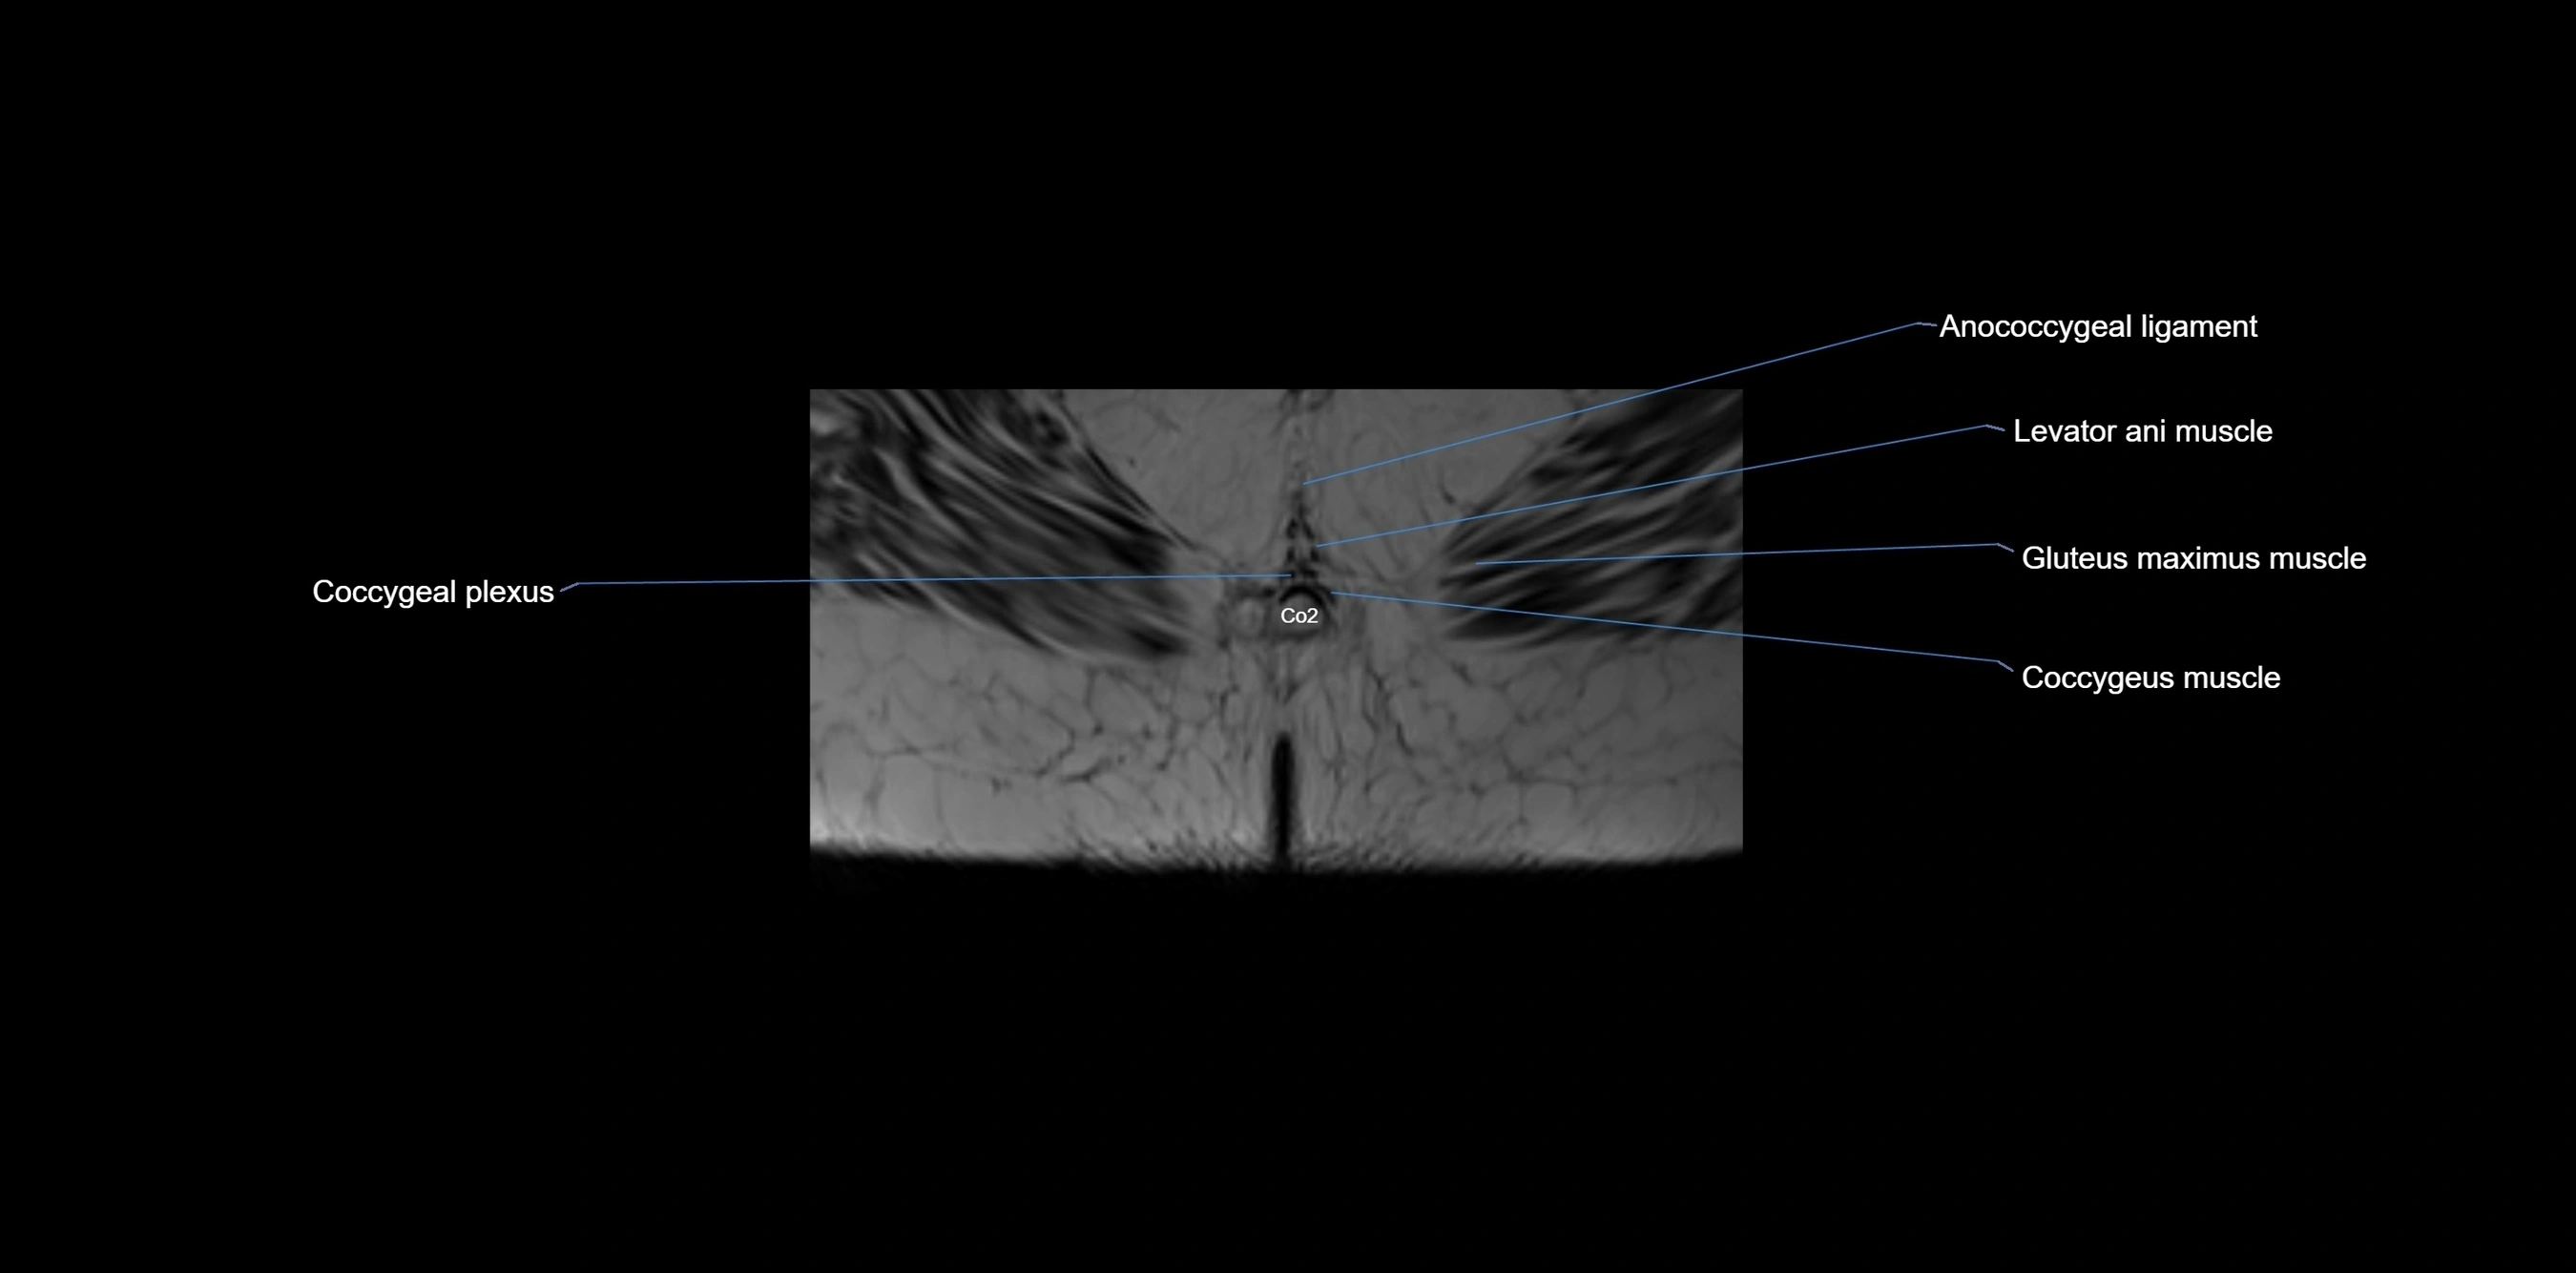

MRI Appearance

T1-weighted images:

• Cortical bone appears very low signal (dark); marrow shows intermediate signal

• Iliac fossa fat is bright against low-signal cortex

T2-weighted images:

• Cortical bone remains dark

• Marrow signal varies depending on fat content; edema or tumor shows hyperintensity

STIR:

• Suppresses fat, making bone marrow edema, fractures, or infiltrative lesions appear bright

• Excellent for trauma, sacroiliitis, and metastatic evaluation

T1 Fat-Saturated (Pre-contrast):

• Marrow: intermediate signal, fat suppressed

• Useful for detecting subtle marrow abnormalities adjacent to iliac cortex

T1 Fat-Saturated Post-Contrast (Gadolinium):

• Enhances vascularized structures, marrow pathology, tumors, and inflammatory changes

• Highlights soft tissue or bone invasion in pelvic neoplasms

MRI Non-Contrast 3D Imaging:

• Provides 3D morphology of iliac wing, crest, and articulations

• Used in preoperative planning for pelvic surgery and trauma reconstruction